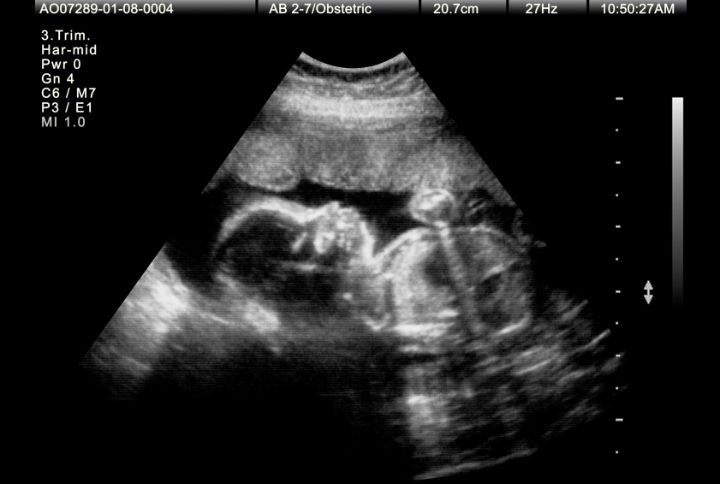

Echographie du 3e trimestre

L’échographie du 3e trimestre de grossesse est la dernière échographie programmée avant l’accouchement, si celui-ci se présente sans complications. Elle se révèle particulièrement importante pour évaluer le poids du bébé, mais aussi pour s’assurer que le fœtus a poursuivi un bon développement. Voici tout ce que vous devez savoir au sujet de l’échographie du 3e trimestre.

À l'instar des deux précédentes échographies, la 3e échographie de grossesse se déroule en position allongée sur le dos. Le médecin applique un gel sur le ventre pour favoriser la pénétration des ultrasons. Puis une sonde balaie le ventre de la mère et permet d’observer le fœtus à l’écran. Il est recommandé, comme pour chacune des échographies, de ne pas appliquer de gel anti- vergetures sur le ventre dans les 24 heures qui précèdent le rendez-vous avec l’échographiste.

Observation de l’environnement du fœtus : contrôle de la position fœtale, qui idéalement est une position avec la tête du bébé vers le bas. L’échographie vérifie également la position et l’aspect du placenta, de même que la quantité de liquide amniotique disponible.